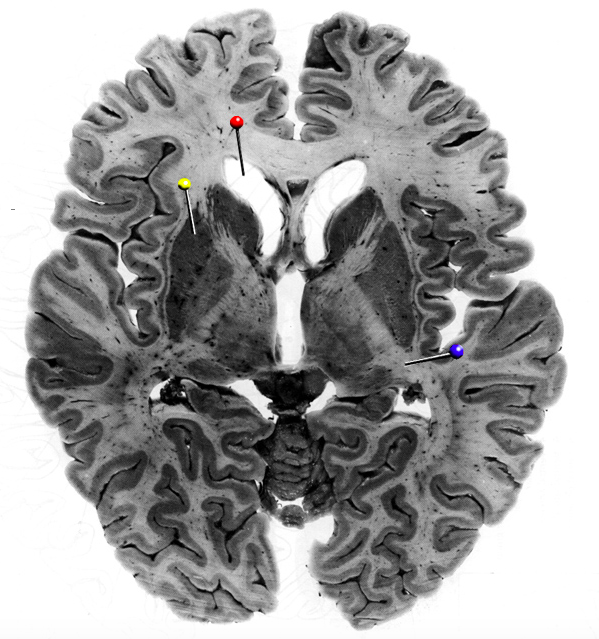

In this horizontal brain slice, the yellow pin is in

What is the structure indicated by the black pin?

What fibres is the structure marked by the black pin made up of?

Commisural fibres

In this horizontal brain slice, the yellow pin is in the…

putamen